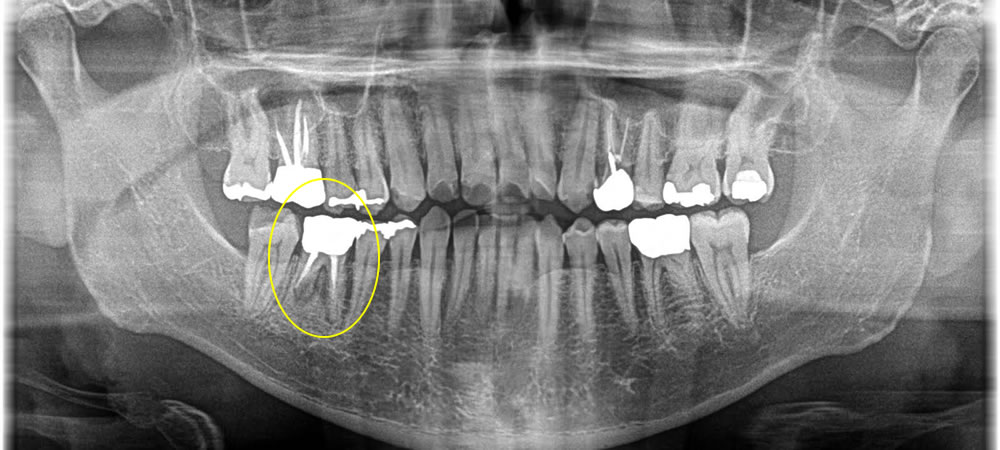

銀歯の下の虫歯を除去後にセラミックインレーで治療した症例

年齢

30代

性別

男性